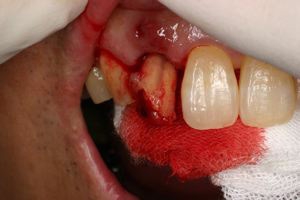

前歯即時埋入症例

術前術前主訴-前歯が腫れて痛い。治療法のうち、ブリッジとインプラントを説明して隣の前歯を削らないですむことからインプラントを選択された。 術前レントゲン術前レントゲン術前レントゲン 抜歯抜歯抜歯を行う。折れていた位置がかなり深い位置であるのがわかる。 歯根も抜歯歯根も抜歯

歯根も抜歯歯根も抜歯歯根も抜歯 抜歯した穴をよく掃除抜歯した穴をよく掃除抜歯した穴をよく掃除(掻爬)後すぐにインプラントを埋入 埋入直後のレントゲン埋入直後のレントゲン埋入直後のレントゲン。上部に見えるのは抜いた歯を利用して両どなりの歯に接着して一時的に使えるようにした。 二次オペ時二次オペ時